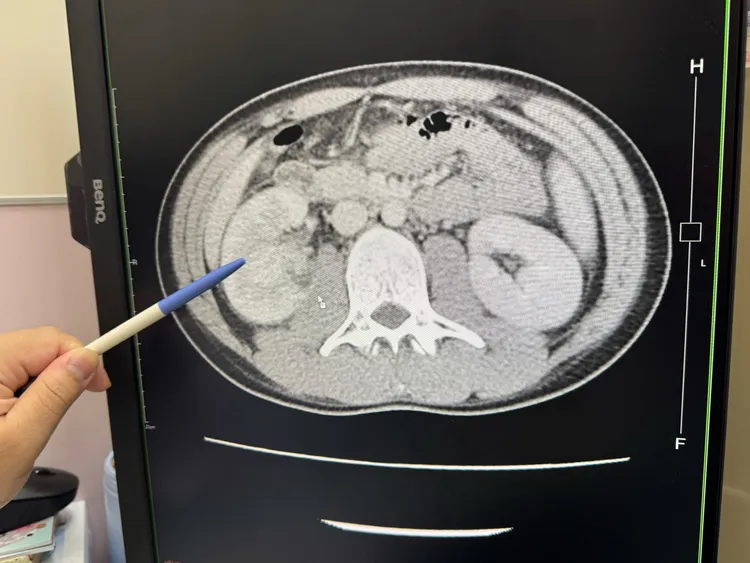

大甲李綜合醫院泌尿科主治醫師黃品叡表示,患者因反覆發燒找不出原因、出現畏寒而自行到急診就醫,檢查後發現,右邊腎臟有兩個0.1公分小的結石,而且右腎腫大是左腎的一倍大,發炎指數飆高到27 mg/dL,是一般正常0.3 mg/dL的90倍,趕緊安排住院治療。

23歲男子每天喝2杯半糖手搖飲,不喝開水,結果罹患急性腎盂腎炎,一邊腎臟腫大一倍大。大甲李綜合醫院提供